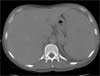

Blood pressure is 118/67 mm Hg; heart rate, 120 beats per minute; respiration rate, 34 breaths per minute; and temperature, 37.4°C (99.3°F). Skin and conjunctivae are pale without petechiae or purpura. The abdomen is protuberant. A CT scan of the abdomen reveals massive splenomegaly (Figure 1). There is no lymphadenopathy.